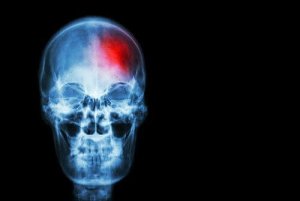

Aivohalvauksen merkit ja niiden tunnistaminen ajoissa voi pelastaa hengen. Aivohalvaukset liittyvät usein korkeaan verenpaineeseen,liikkumattomaan elämäntapaan ja elimistön liian suureen vapaiden radikaalien määrään. Halvausriski on suurempi myös silloin, jos polttaa tupakkaa, juo liikaa alkoholia sekä stressaa paljon.

Kun verta ei kulkeudu riittävästi aivoille, solut eivät saa tarvitsemiaan ravintoaineita ja happea toimiakseen kunnolla, jolloin ne lopulta kuolevat.

Aivoverisuonisairaudet ovat kolmanneksi yleisin kuolemaan johtava syy länsimaissa ja suurin syy saada pysyvä vamma. Ne ovat myös yksi neurologisten ongelmien laukaisijoista vanhemmilla ihmisillä.